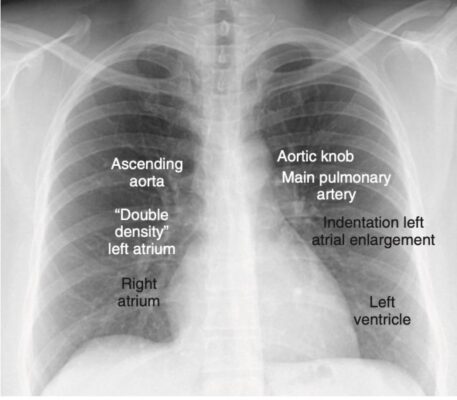

Các đường viền tim bình thường bao gồm một các đoạn lồi và lõm có thể nhìn thấy trên phim chụp X quang ngực thẳng (Hình 2).

Có thể xác định được bảy đường viền tim trên phim chụp X quang ngực thẳng.

- Ở phía bên phải của tim, đường viền đầu tiên là một cạnh gần như thẳng, mật độ thấp, có thấy được ngay bên cạnh khí quản phản ánh kích thước của động mạch chủ lên.

- Nơi đường viền của động mạch chủ lên gặp đường viền của tâm nhĩ phải, thường có một ấn lõm nhẹ ở đó tâm nhĩ trái có thể xuất hiện khi nó bị to ra (gọi là dấu hiệu mật độ kép, double-density sign).

- Đường viền tim phải được tạo thành bởi tâm nhĩ phải.

- Ở bên trái, đường viền đầu tiên là núm động mạch chủ, một hình ảnh x quang được tạo bởi cung động mạch chủ chồng lên một phần của đoạn đầu của động mạch chủ xuống.

- Đường viền tiếp theo bên dưới núm động mạch chủ là động mạch phổi chính, trước khi nó chia thành động mạch phổi phải và trái.

- Ngay dưới đoạn động mạch phổi chính thường có một vết lõm nhẹ nơi tâm nhĩ trái phì đại có thể xuất hiện ở phía bên trái của tim.

- Đường viền cuối cùng của tim bên trái được tạo thành bởi tâm thất trái.

- Động mạch chủ xuống gần như không nhìn thấy được với bóng của cột sống.